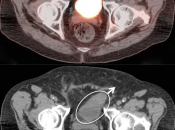

Bladder Hernia

While the CT appearance of this finding should never be missed, its striking PET appearance has led more than one PET/CT reader astray.

Usually, the supero-lateral margin of the bladder will be seen partially entering the inguinal canal. Occasionally, a significant segment of the bladder may extend deep into the hernia defect.

Caveat: Never be duped by an unusual focus of intense metabolic activity anywhere in the body. Always rule out every possible non-neoplastic explanation before raising the specter of cancer.